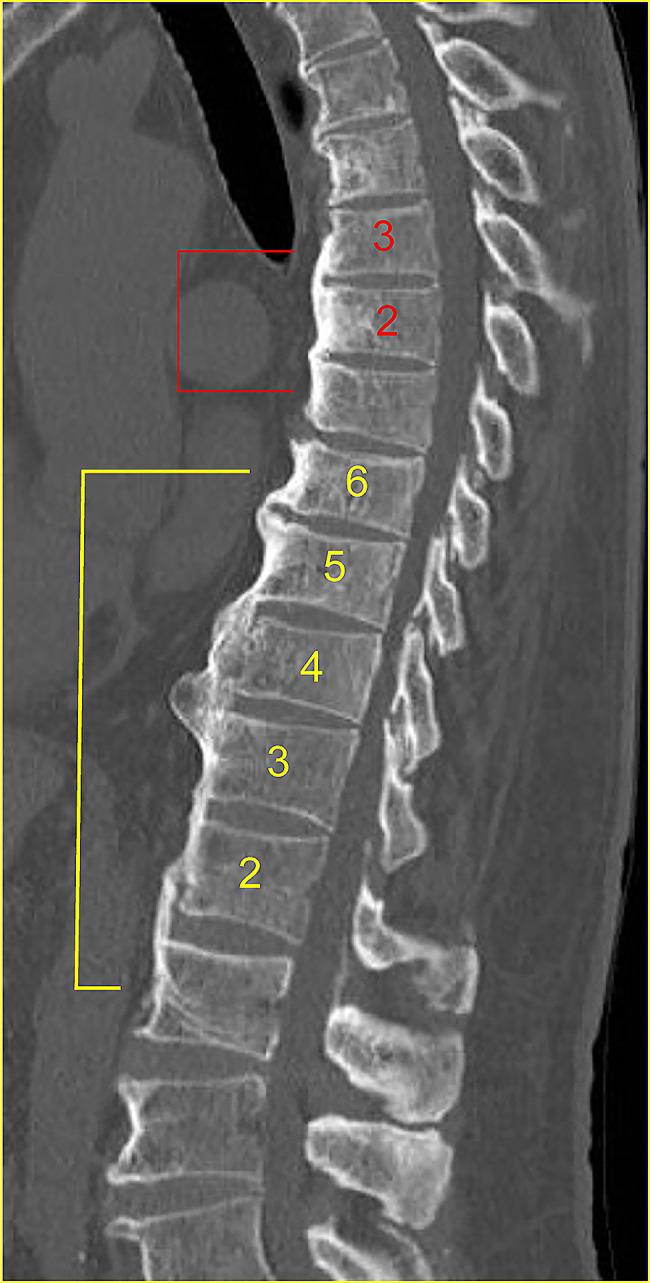

To achieve good bone fusion in anterior column reconstruction for vertebral fractures, not only bone mineral density (BMD) and bone metabolism markers but also lever arms due to bone bridging between vertebral bodies should be evaluated. However, until now, no lever arm index has been devised. Therefore, we believe that the maximum number of vertebral bodies that are bony and cross-linked with the contiguous adjacent vertebrae (maxVB) can be used as a measure for lever arms. The purpose of this study is to investigate the surgical outcomes of anterior column reconstruction for spinal fractures and to determine the effect of bone bridging between vertebral bodies on the rate of bone fusion using the maxVB as an indicator of the length of the lever arm.

The clinical data of 81 patients who underwent anterior column reconstruction for spinal fracture between 2014 and 2022 were evaluated. The bone fusion rate, back pain score, between the maxVB = 0 and the maxVB ≥ 2 patients were adjusted for confounding factors (age, smoking history, diabetes mellitus history, BMD, osteoporosis drugs, surgical technique, number of fixed vertebrae, materials used for the anterior props, etc.) and analysed with multivariate or multiple regression analyses. The bone healing rate and incidence of postoperative back pain were compared among the three groups (maxVB = 0, 2≦maxVB≦8, maxVB ≧ 9) and divided by the maxVB after adjusting for confounding factors.

为了实现椎体骨折前柱重建中的良好骨融合,不仅需要评估骨矿物质密度(BMD)和骨代谢标志物,还需要评估由于椎体间骨桥形成而导致的力臂。然而,到目前为止,还没有设计出力臂指数。因此,我们认为可以使用与相邻椎体骨性和交联的最大椎体数(maxVB)作为力臂的测量指标。本研究的目的是探讨前路重建治疗脊柱骨折的手术效果,并通过使用 maxVB 作为力臂长度的指标来确定椎体间骨桥形成对骨融合率的影响。

回顾性分析 2014 年至 2022 年间接受前路重建治疗脊柱骨折的 81 例患者的临床资料。调整混杂因素(年龄、吸烟史、糖尿病史、BMD、骨质疏松症药物、手术技术、固定椎体数、前路支撑材料等)后,比较 maxVB=0 和 maxVB≥2 患者的骨融合率和腰背疼痛评分,并进行多变量或多元回归分析。调整混杂因素后,根据 maxVB 将患者分为 3 组(maxVB=0、2≦maxVB≦8、maxVB≧9),比较各组间的骨愈合率和术后腰背疼痛发生率。